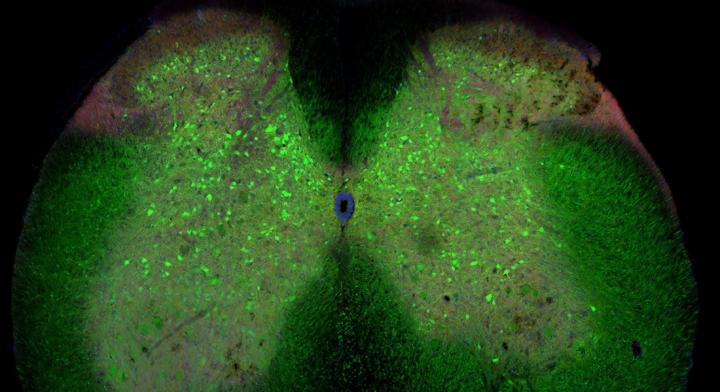

image: The spinal cord of a mouse with ALS. The green cells are inhibitory interneurons. view more

Credit: Ilary Allodi, University of Copenhagen